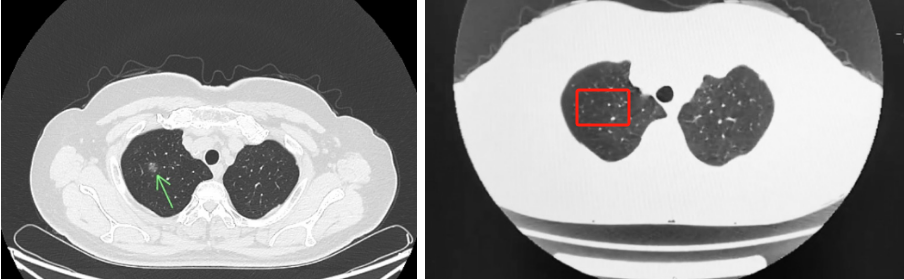

近日,91porn (湖北省中山91porn )中医科成功运用中医药疗法,帮助一位1.1厘米的肺结节患者李奶奶避免了手术治疗。复查CT时,放射科医生也惊喜表示:“一个月前还清晰可见的1.1厘米结节,现在几乎消失!”71岁的李奶奶手持显示结节仅余2-3毫米的报告单,喜悦之情溢于言表。此前,她因外院建议手术而深陷焦虑,最终选择中医治疗。

中药复方通过多靶点调控,有效逆转局部炎性微环境,促进异常增生组织的消散与吸收,一段时间后,李奶奶结节的明显缩小。目前,李奶奶仍在门诊随访调治,结节稳定未见反复,困扰多年的咽部异物感、睡眠质量也得到改善。她感慨道:“没想到几副汤药,竟能化解开胸之忧!”